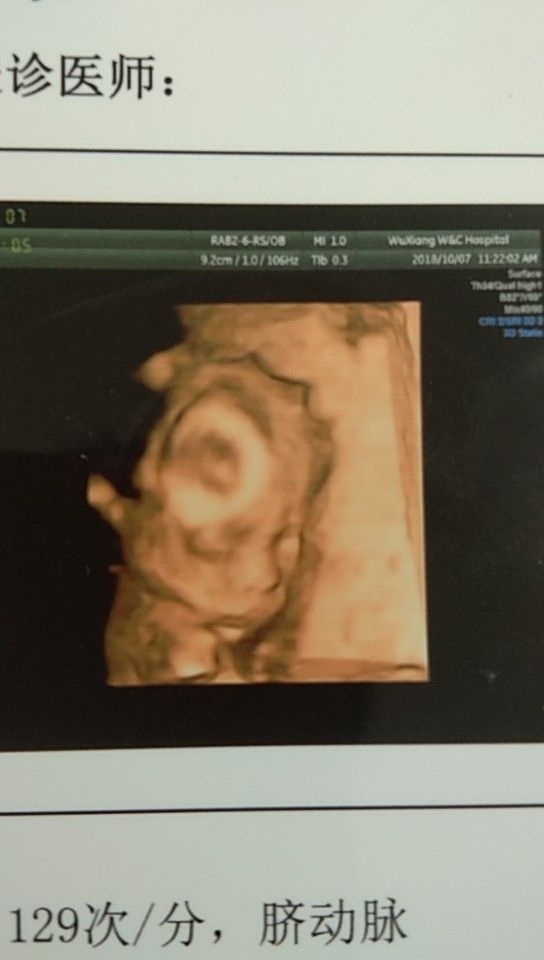

孕22周+5天

孕12周+1天